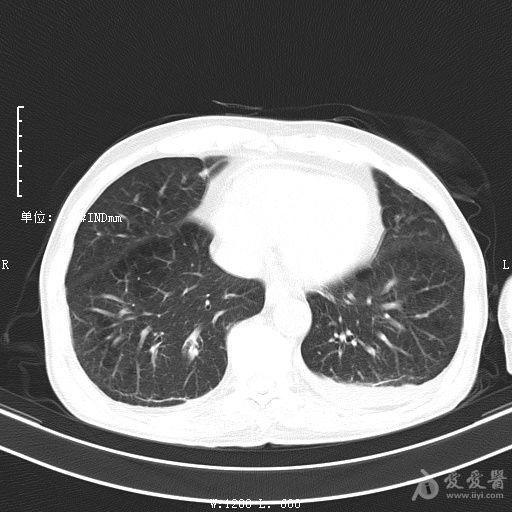

最新的肺炎疫情形勢嚴峻,病毒變異使得防控工作更加復雜,許多地方出現(xiàn)了新的病例,甚至有些地區(qū)的疫情出現(xiàn)了反彈,這不僅是對醫(yī)療系統(tǒng)的考驗,更是對每一個生命的考驗,我們需要密切關注疫情動態(tài),共同應對這場挑戰(zhàn)。??